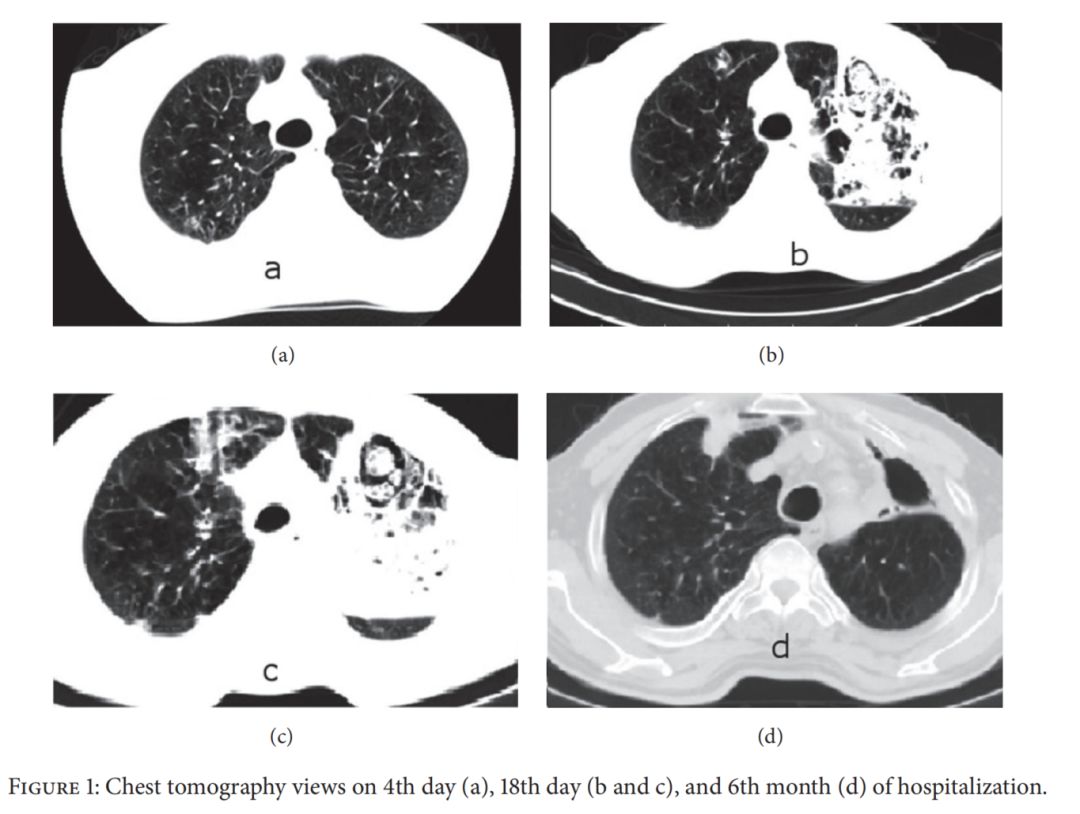

慢阻肺合并肺念珠菌感染确诊率低,国外仅有少量病例报道,国内研究以临床诊断为主。这是国外的一例典型病例:

66岁男性患者,诊断慢阻肺5年,长期吸入福莫特罗、异丙托溴铵。

因咳嗽、咳痰、痰中带血,呼吸困难加重入院。

体查:SpO2 89%。

诊断为光滑念珠菌肺炎,伏立康唑治疗后患者症状改善,复查CT有明显好转。

慢阻肺合并IPA影像表现为空洞、胸腔积液、结节、实变、浸润影。

影像学特点缺乏特异性,以「气道侵袭性」为主。

58岁男性患者,诊断慢阻肺3年。因反复咳嗽咳痰气促3年,再发加重伴咯血1+月入院。

体查:体温:36.0℃,脉搏:87次/分,呼吸:20次/分,血压:166/104mmHg;慢性病容,桶状胸,双侧呼吸动度对称,语颤无增强,双肺叩诊过清音,双肺呼吸音粗,右上肺少许干罗音,双肺未及胸膜摩擦音。

肺部CT:右上肺渗出